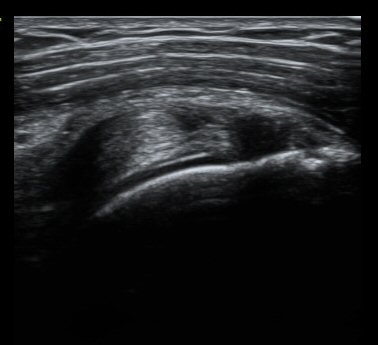

ȸÀü±Ù°³°£°Ý Ⱦ´Ü¸é°Ë»ç¿¡¼­ Á¡¾×³¶³» ¼ö¾×Àú·ù°¡ °üÂûµÈ´Ù(±×¸² 1). ÀÌµÎ¹Ú±Ù°Ç °í¶û¿¡¼­´Â ƯÀÌ ¼Ò°ßÀ» º¸ÀÌÁö ¾Ê´Â´Ù(±×¸² 2). ȸÀü±Ù°³°£°Ý ³»Ãø¿¡¼­ °ß°©ÇϱٰÇÀÇ ÆÄ¿­°ú Á¡¾×³¶³» ¼ö¾×Àú·ù°¡ °üÂûµÈ´Ù(±×¸² 3, 4). ±Ø»ó°Ç Ⱦ´Ü